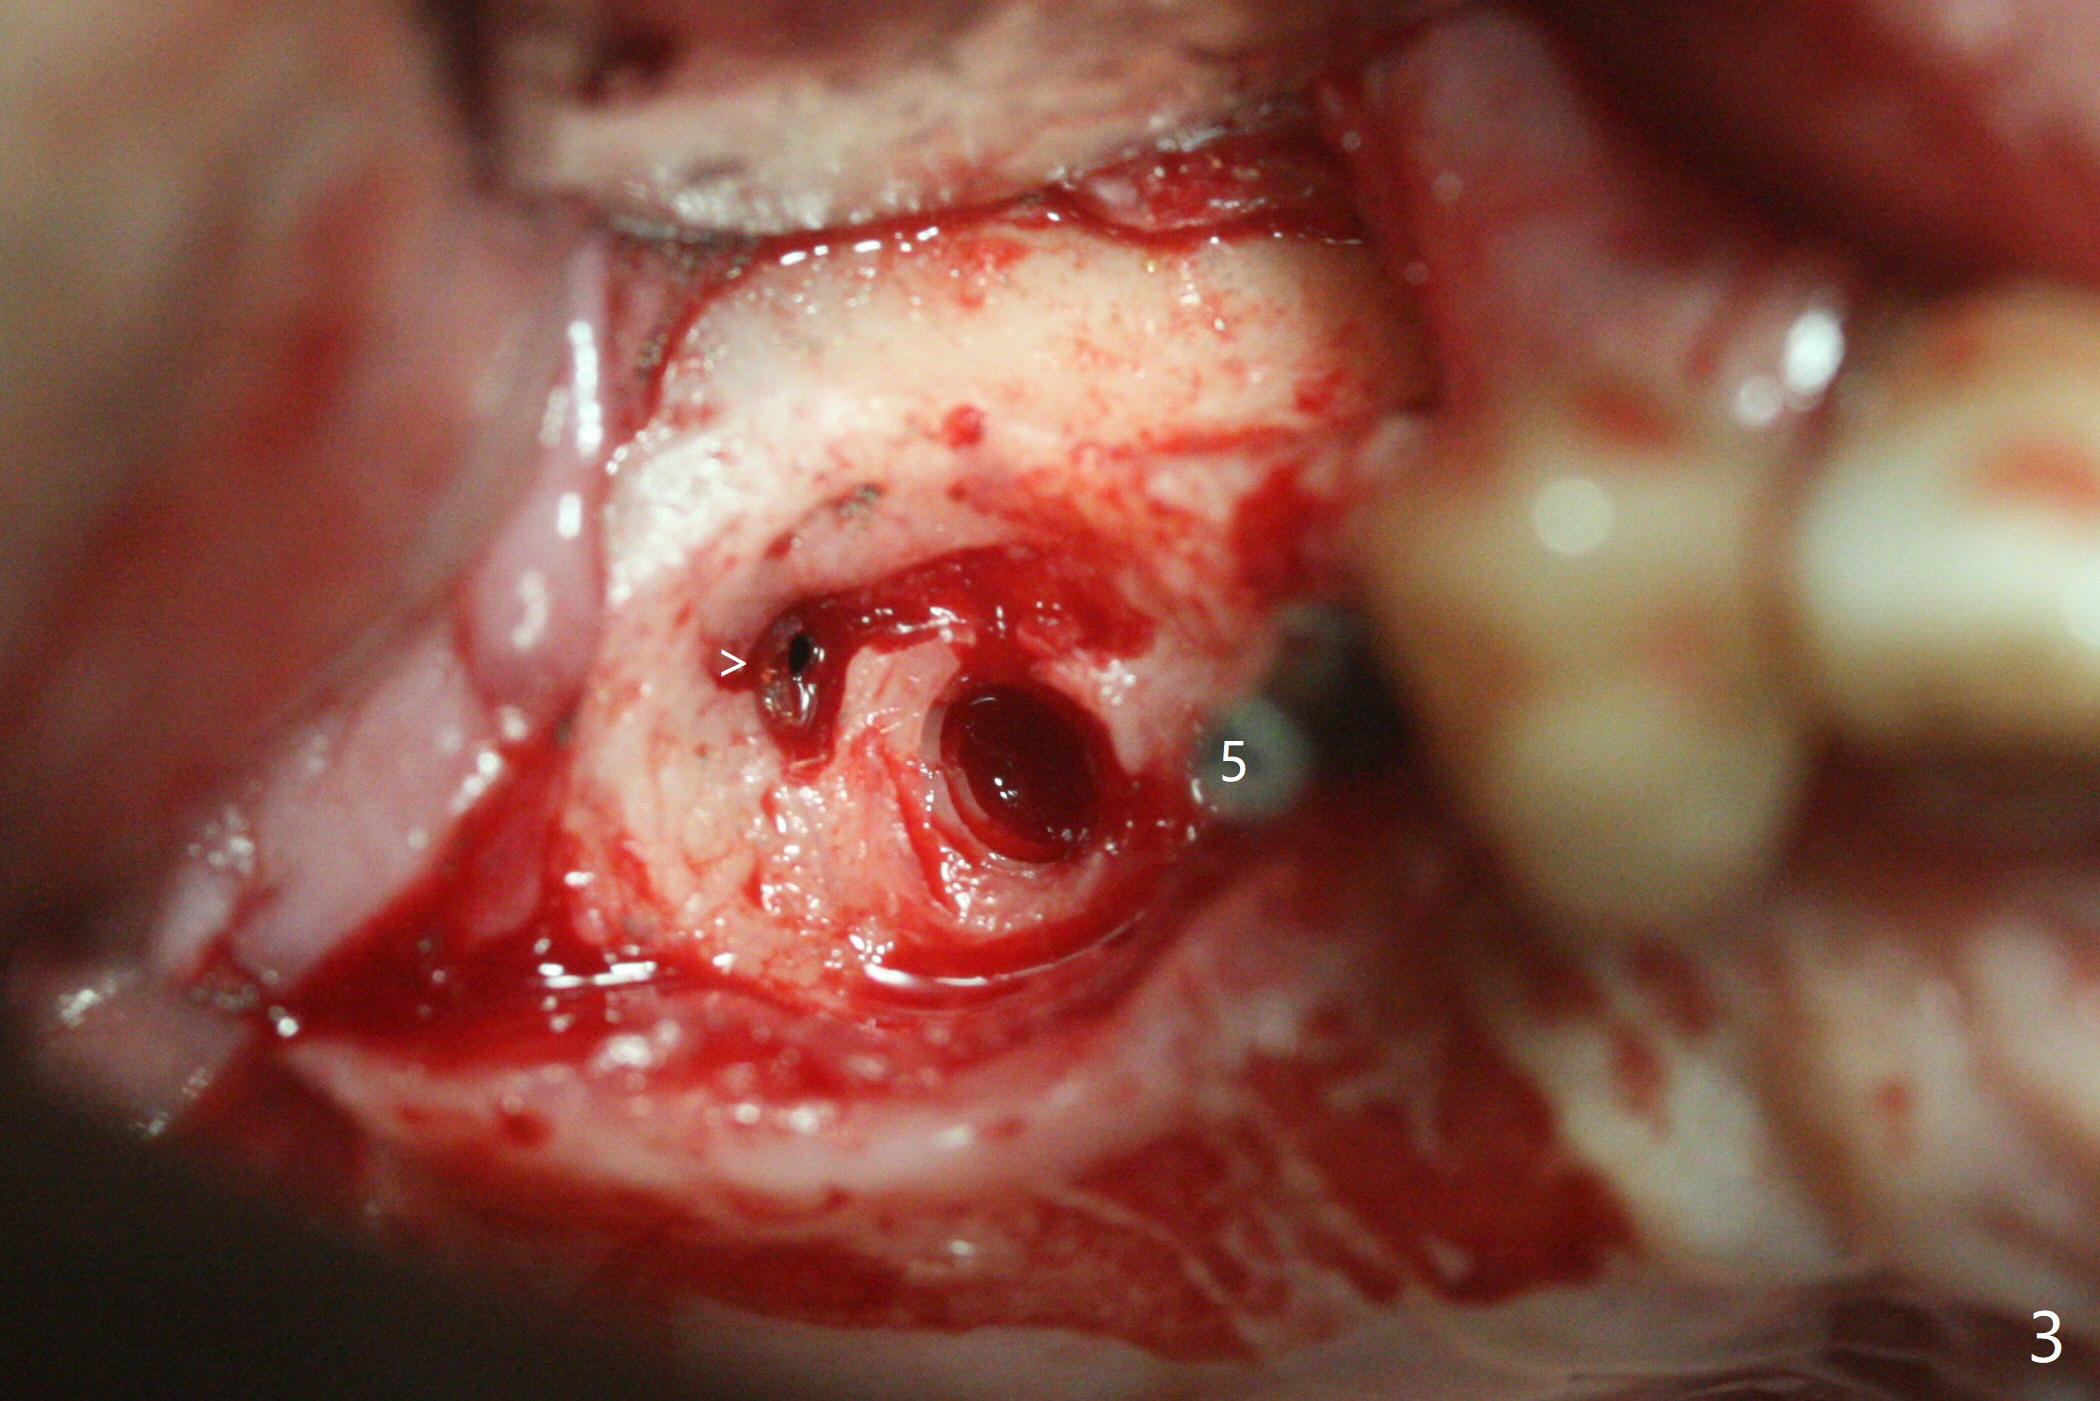

术前检查发现右上6颊侧牙龈沟有脓性分泌物(图一),翻瓣显示骨质吸收(图二),曾经植骨三次,只好去骨,取出植体,远中颊侧轻度上颌窦穿孔(图三:>),塞入小块PRF膜后,患处放置粘性骨粉,覆盖两块PRF膜和一片GEM Cap(9-12月吸收膜),三者近中一端有一个洞,挂在5基台上固定。术后即刻根尖片显示骨粉充填穿孔(图四:>),6缺失区以及5远中(*)。术后第二天牙周敷料脱落,术后16天病人回来,要求剪除缝线,伤口尚未关闭,下面黄色骨粉好像挺牢靠;为了减少继续骨粉丧失,使用树脂敷料(图五)。术后四周敷料稳定,牙龈健康,但是不放心下面伤口愈合,暂时没有撤去敷料。术后四个月骨质高度不足(图六至八),上颌窦膜薄,提升不容易,可放置5x7.3毫米植体(IBS),PRF。Return to No Caries 4 Placement 种植杂谈 Xin Wei, DDS, PhD, MS 1st edition 01/26/2021, last revision 07/30/2021